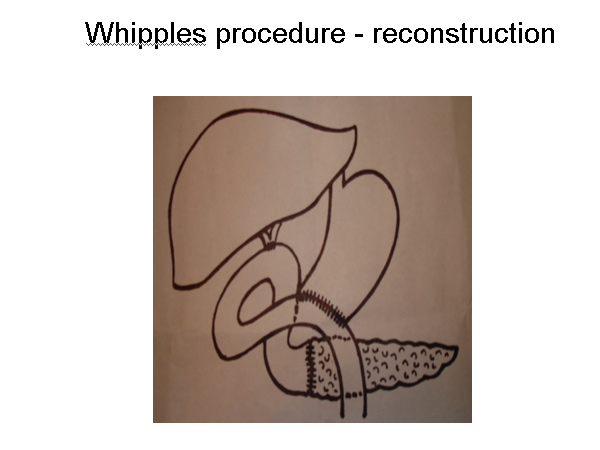

ancreas is an organ situated in the upper part of the abdomen behind the stomach. It produces digestive enzymes to help in digestion of food products and also produces insulin which is essential for sugar control. Pancreatic juices are secreted in the intestines through the main pancreatic duct. The main pancreatic duct joins the common bile duct to open into the duodenum.